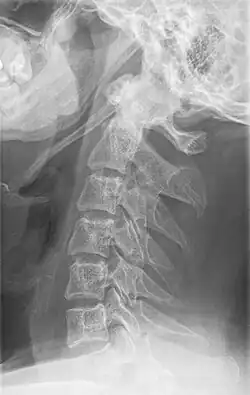

Imaging is important and is diagnostic. Visualizing the styloid process on a CT scan with 3D reconstruction is the suggested imaging technique.[13] The enlarged styloid may be visible on an orthopantogram or a lateral soft tissue X ray of the neck.